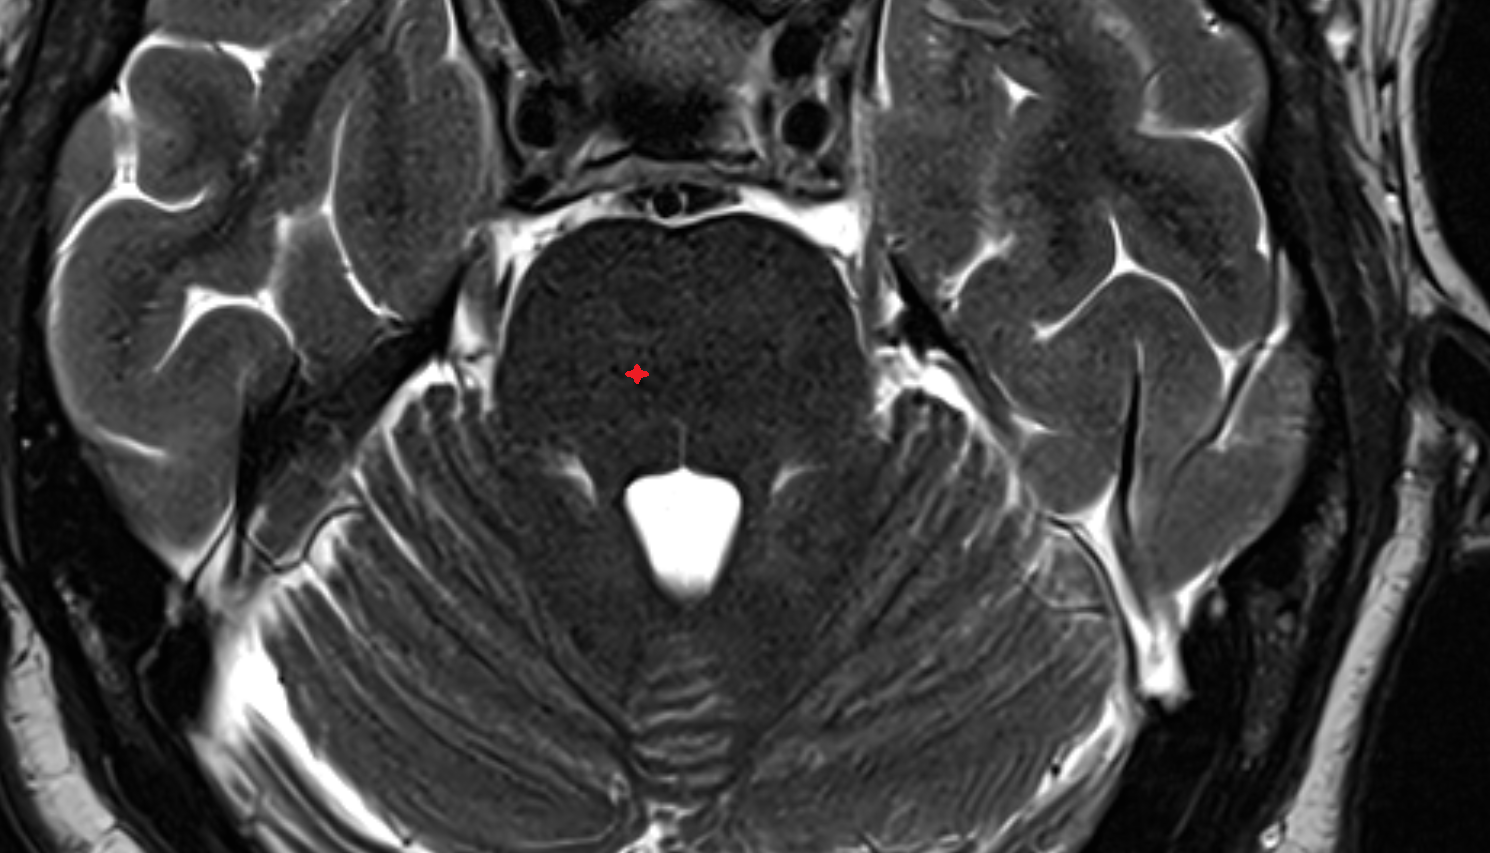

- Cerebellum

- Pons